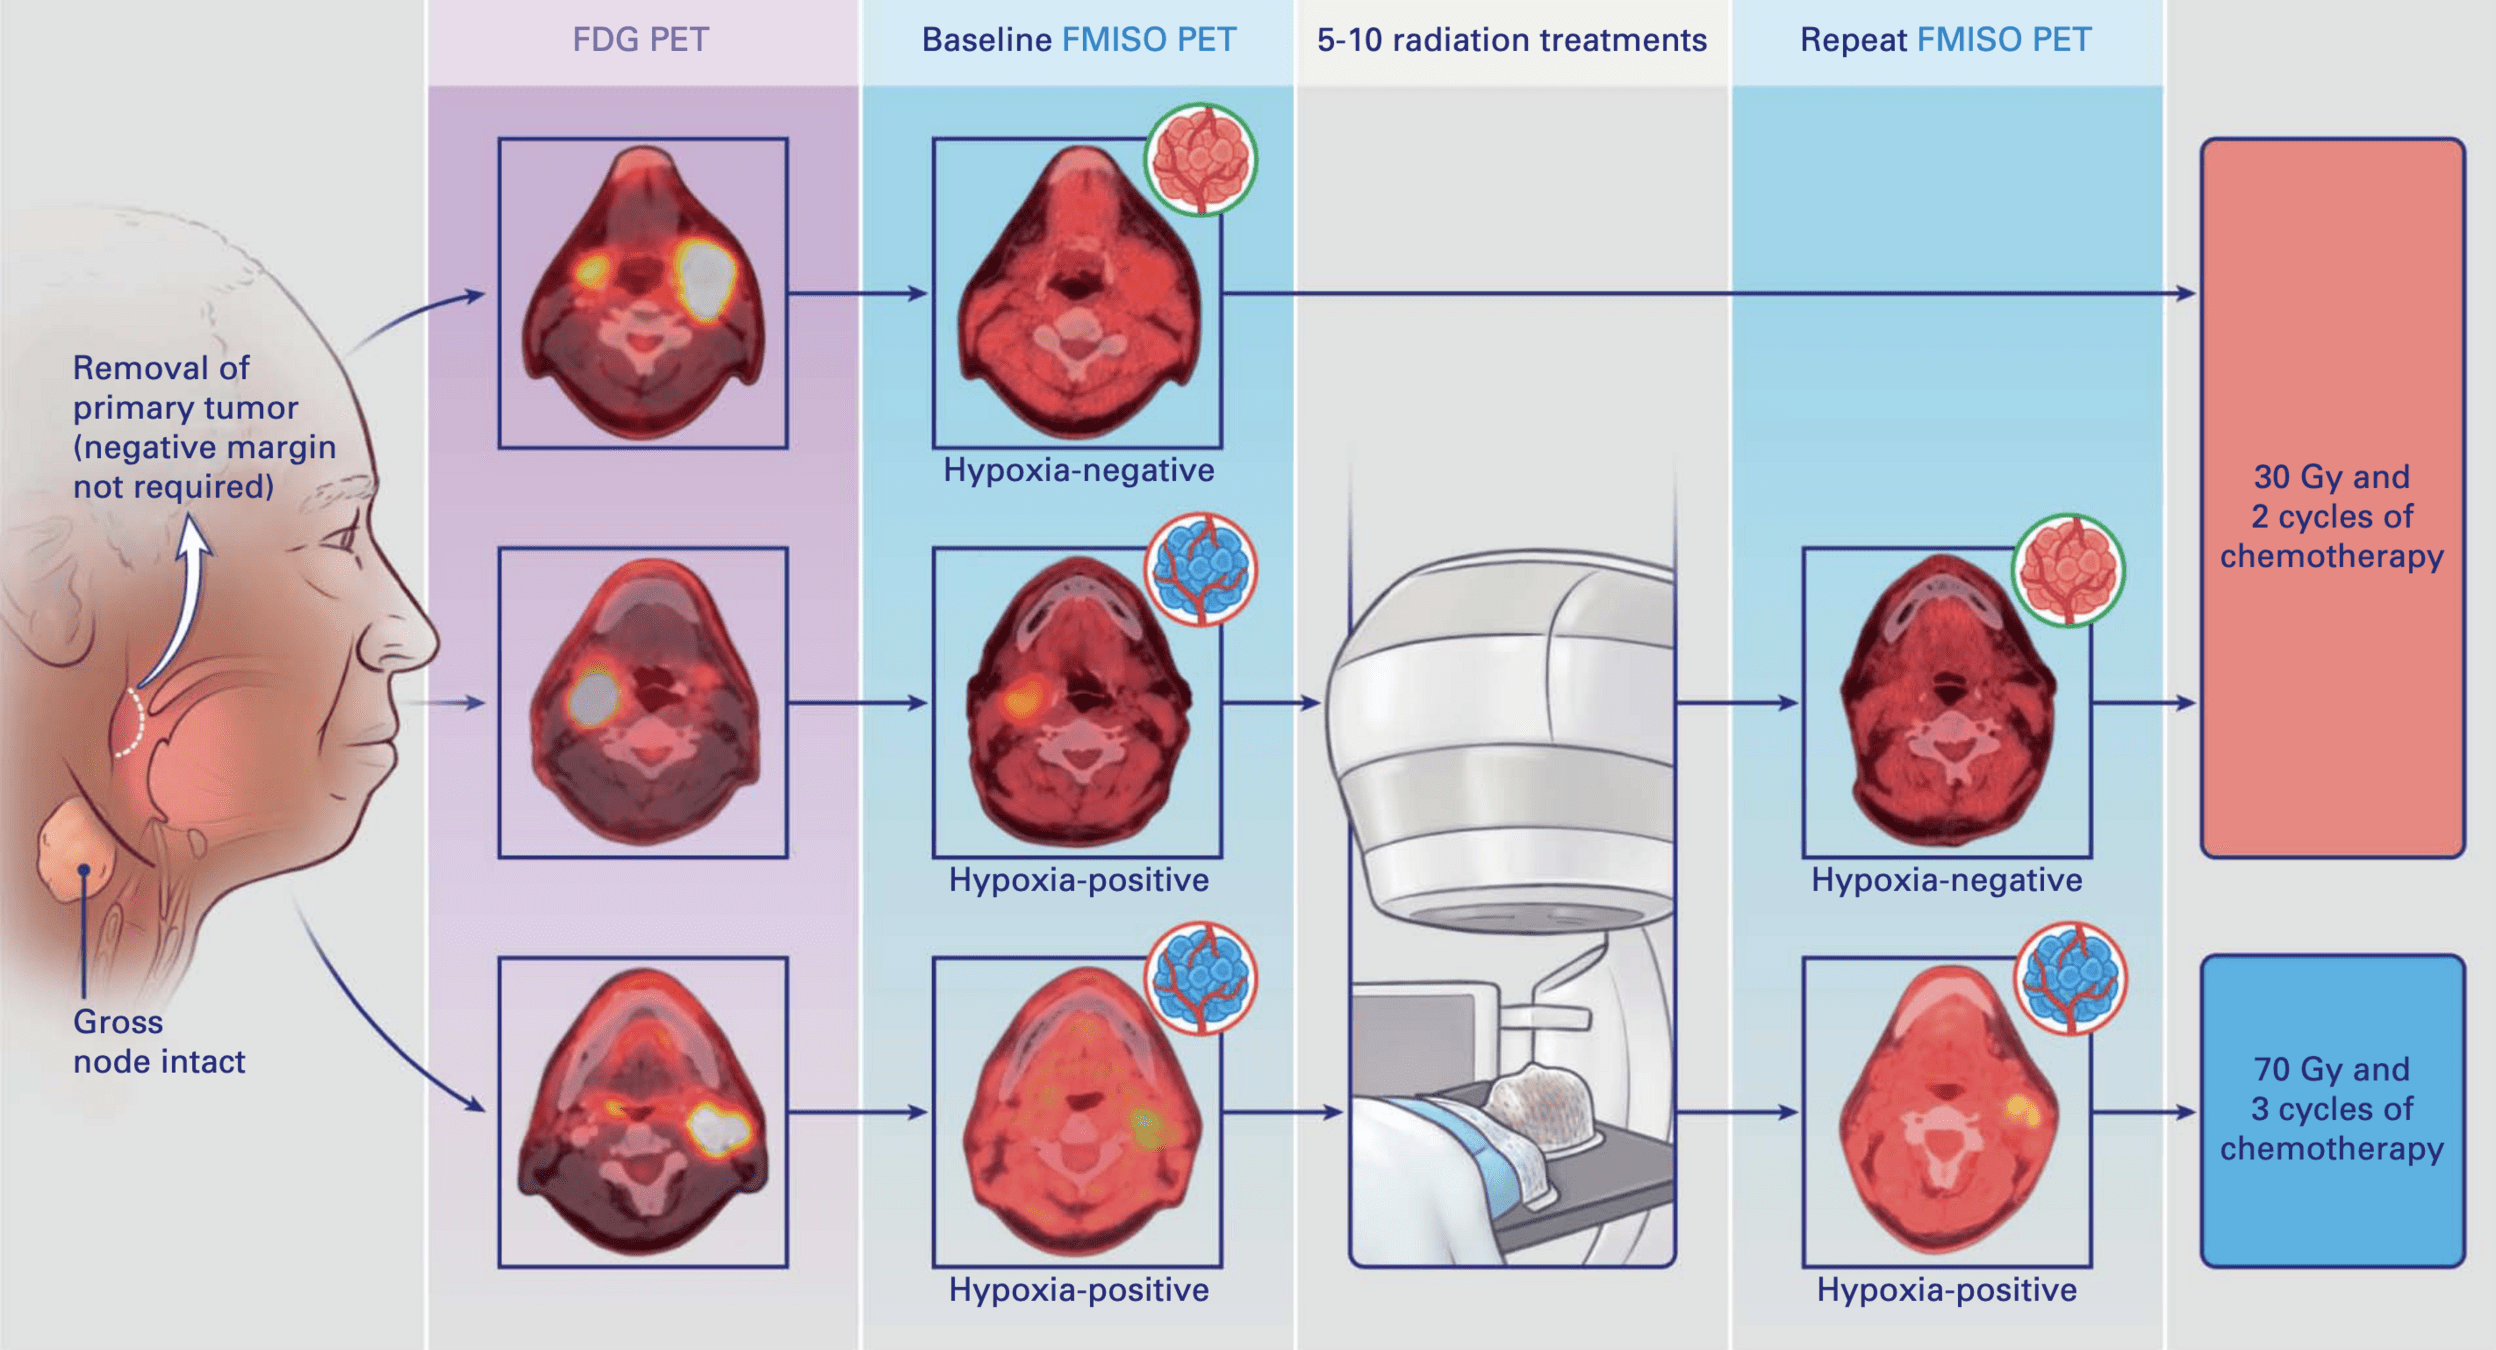

Study Hypothesis

- Tumors without hypoxia can be treated with significantly lower radiation doses

- FMISO PET can identify patients eligible for de-escalation from 70 Gy to 30 Gy

- 30 Gy dose based on curative dose for HPV-related anal cancer

- Pilot study (n=19): 87% pathologic response with 30 Gy in non-hypoxic tumors

Treatment Allocation

-

30 Gy cohort (84% of patients):

- Baseline FMISO negative OR

- Hypoxia resolution on repeat FMISO

- 15 fractions with concurrent chemotherapy

70 Gy cohort (16% of patients):

- Persistent hypoxia on repeat FMISO

- 35 fractions with concurrent chemotherapy

- Chemotherapy: Cisplatin 100 mg/m² or Carboplatin/5-FU

- All patients had surgical removal of primary tumor